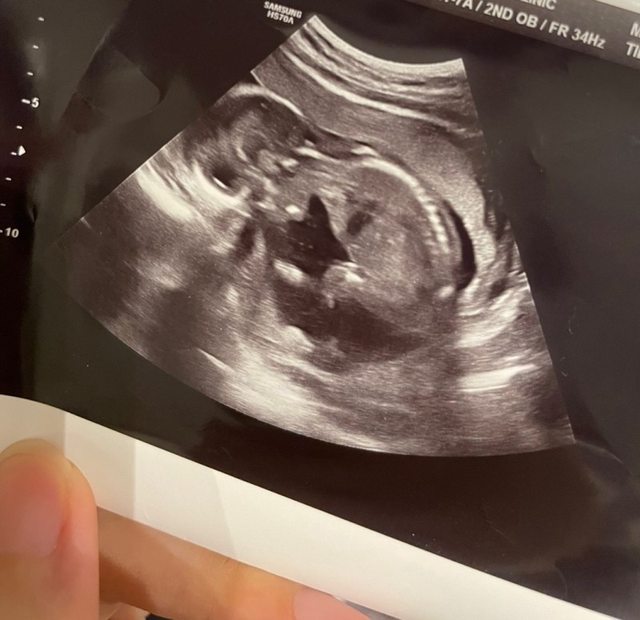

超音波照片 https://i.imgur.com/Opkl8pz.jpg

https://i.imgur.com/sf6Ccue.jpg